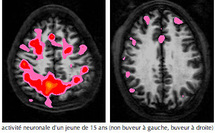

L'activité dans plusieurs régions du cerveau, notamment les capacités d'attention et de mémoire, est réduite à la suite de beuveries chez ces dernières par rapport aux adolescentes qui ne boivent jamais d'alcool, explique Susan Tapert, professeur de psychiatrie à Stanford et co-auteur de l'étude.